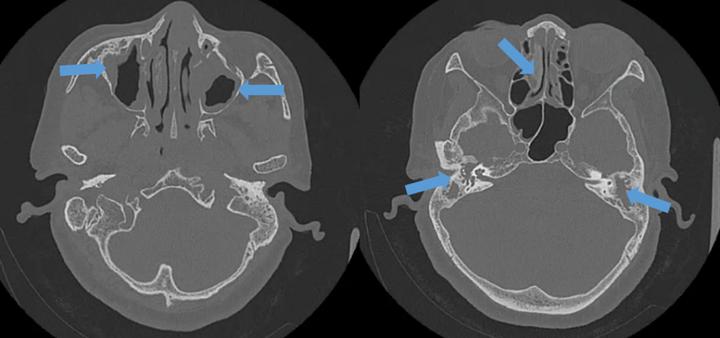

颞骨薄扫CT,箭头(左、右上)示上颌窦炎症,箭头(右下)示双侧中耳乳突炎